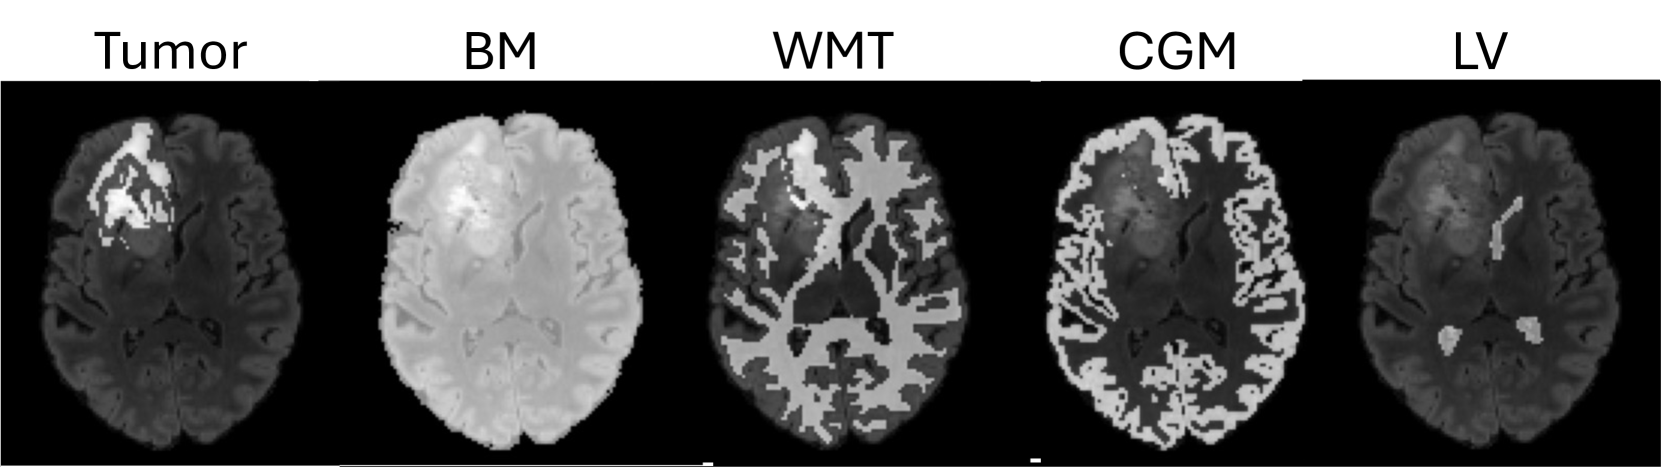

We propose BrainMRDiff, a topology-guided diffusion model designed to preserve the structural details of anatomical regions in synthesized MRI sequences. Our approach conditions the generation process on multiple anatomical masks, including White Matter Tracts (WMT), Cortical Gray Matter (CGM), Lateral Ventricles (LV), Brain Masks (BM), and tumor segmentation masks. Notably, no existing work has investigated the combined utilization of these anatomical structures as conditioning inputs for diffusion-based image synthesis. However, a key challenge remains–—the generated anatomical structures must maintain their topological consistency, particularly in tumor regions, where morphology varies significantly across patients. To tackle this variability, we introduce a topology-preserving loss function that enforces structural fidelity in tumor regions. Our approach bridges a critical gap in medical image generation, ensuring that synthetic MRI scans not only appear realistic but also retain anatomical accuracy, making them more clinically applicable.

Fig. 2 provides an overview of our proposed work, BrainMRDiff. Our goal is to generate anatomically-accurate brain MRI scans. BrainMRDiff consists of two key components: Tumor+Structure Aggregation (TSA) and Topology-guided Anatomy Preservation (TGAP). The TSA module combines anatomical structures such as the Brain Mask (BM), White Matter Tract (WMT), Cortical Gray Matter (CGM), and Lateral Ventricles (LV) with tumor masks to provide conditional control to the diffusion model. These masks ensure spatial correctness and detail preservation of the anatomical structures in the generated image. While these conditional controls significantly improve the generated image quality for BM, WMT, CGM, and LV, they are still not powerful enough to capture the heterogeneity of tumor regions. To capture irregular tumor patterns, we propose stronger constraints to guide the diffusion model. Specifically, we propose the TGAP module to enforce topological constraints. It does so by leveraging tools such as persistent homology [21, 22] and diagrams from topological data analysis [14]. Enforcing topological constraints ensures higher-fidelity tumor region generation.

Brain anatomy. In addition to the tumor, we use several other anatomically important structures namely White Matter Tracts (WMT), Cortical gray Matter (CGM), Lateral Ventricles (LV), and Brain Masks (BM). The detailed explanation about the generation of the structures are discussed in Sec. 4.1. In Fig. 3, we show examples of the different structures. More examples are shown in Supplementary (Figure 10).